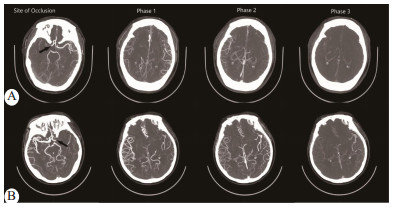

根据Menon等[2]提出的Alberta Stroke Program Early CT Score (ASPECTS)侧支循环六点量表,按头颅mCTA显示的患侧MCA供血区软脑膜吻合支代偿速度及充盈数量,认为ASPECTS侧支循环评分>3分为侧支循环良好,≤3分为侧支循环不良(图 1)。侧支循环评估由工作多年的三位放射科医师采用盲法分别对研究对象的mCTA进行,若有争议以多数意见为准。据此分为侧支良好组和侧支不良组,分别有31例和18例。

A:55岁女性,NIHSS 11分,mCTA显示RMCA闭塞,ASPECTS侧支循环得分为4分,表明侧支循环良好;B:51岁女性,NIHSS 14分,mCTA显示LMCA闭塞,ASPECTS侧支循环得分为2分,表明侧支循环不良 图 1 采用ASPECTS侧支循环六点量表评分法对患者进行侧支水平评估 Fig 1 Assessment of collateral levels in patients using the ASPECTS collateral circulation six-point scale